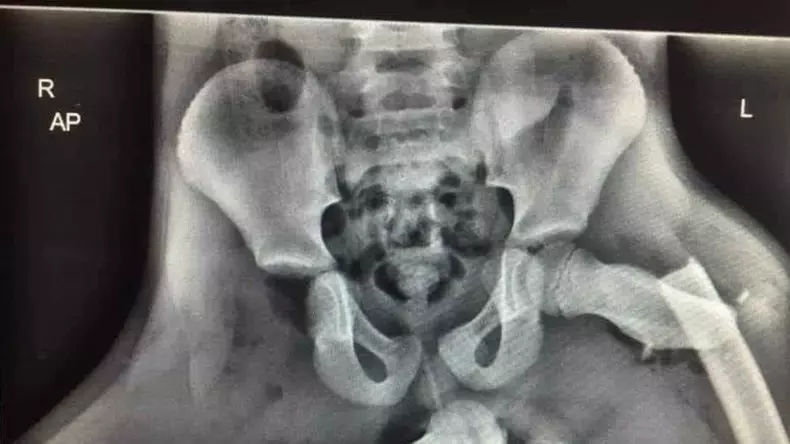

Ce poți păți într-un accident dacă îți ții picioarele pe bord